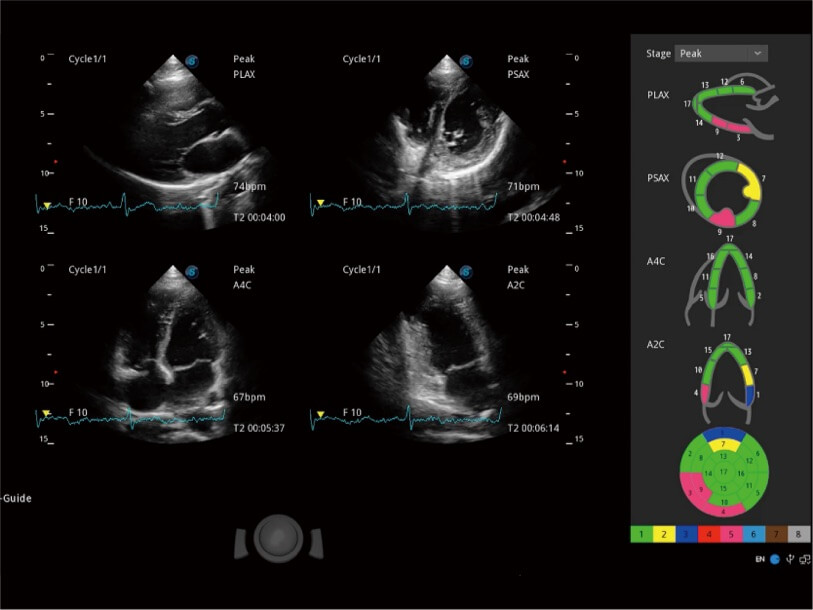

Die präzise Erkennung der linksventrikulären Wandbewegung mit globalem 2D-Speckle-Muster-Tracking ermöglicht eine genaue quantitative Analyse einschließlich Dehnung, Dehnungsrate, Auslenkung, Geschwindigkeit usw. der Myokardwände.

Erfasst multiple dynamische Bilder in Ruhe und nach Belastung für den Vergleich Seite bei Seite. Für eine weitergehende effektive Abklärung der Vitalität des Herzmuskels werden professionelle Scores und Berichte zur Wandbewegung des Tieres bereitgestellt.